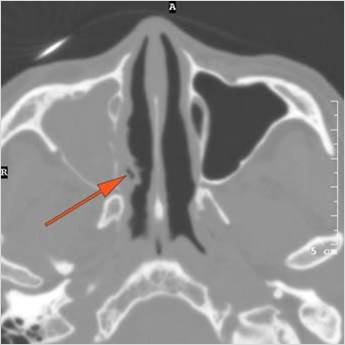

There is infiltration of soft tissues or bone erosion along the nasolacrimal fossa or canal.